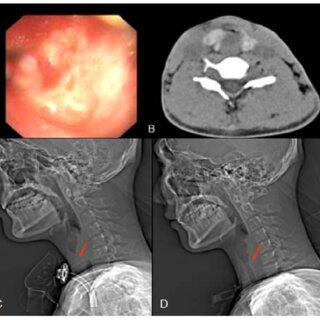

Interventional radiology uses advanced imaging techniques to guide medical procedures inside the body. Doctors view the treatment area in real-time using X-rays, ultrasound, or CT scans while performing the procedure. This approach enables the precise targeting of tumors while protecting the surrounding healthy tissue.

The specialty focuses on treating various conditions through minimally invasive procedures rather than open surgery. Doctors insert thin tubes, needles, or probes through the skin to reach the treatment area. The imaging technology helps them navigate to the exact location where treatment is needed. The precision of image-guided procedures makes them particularly helpful for tumors that are difficult to reach through traditional surgery.

Tumor ablation destroys cancer cells by applying extreme temperatures or chemical agents directly to the tumor. The procedure uses specialized probes or needles that are guided to the tumor location using imaging technology. Once positioned correctly, the doctor activates the ablation device to destroy the cancerous tissue.

Different types of ablation techniques target tumors in various ways. Radiofrequency ablation uses heat generated by radio waves to destroy cancer cells. Microwave ablation generates heat through the application of microwave energy. Cryoablation freezes tumors using extremely cold temperatures to kill cancer cells. The destroyed tumor tissue remains in the body but gradually gets absorbed over time. The body’s natural healing process removes the dead tissue while healthy tissue around the treatment area remains intact.